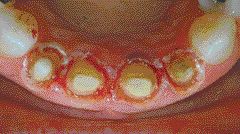

Predictable “Gum Lifts” Made Easy

FIGURE 6A & B--Circumferential gingivectomies and soft tissue curettage accomplished with electrosurgery to obtain the desired contours and eradicate the infection.

Beautiful porcelains and strong bonding materials have made excellent cosmetic dentistry possible, but the true artistry is in the smile design and one of the most important elements of good smile design is the gingival contour. In order to achieve a beautiful smile design the contours of the teeth and gingiva must be harmonious with … Read more